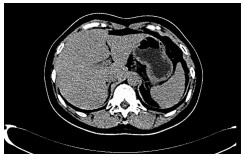

2型糖尿病合并糖原性肝病1例报告

马仁舒, 武彤, 于鸽, 丛莹, 辛桂杰

2021, 37(9): 2183-2184. DOI: 10.3969/j.issn.1001-5256.2021.09.035

摘要(703) HTML (445) PDF (3125KB)(57)

摘要: